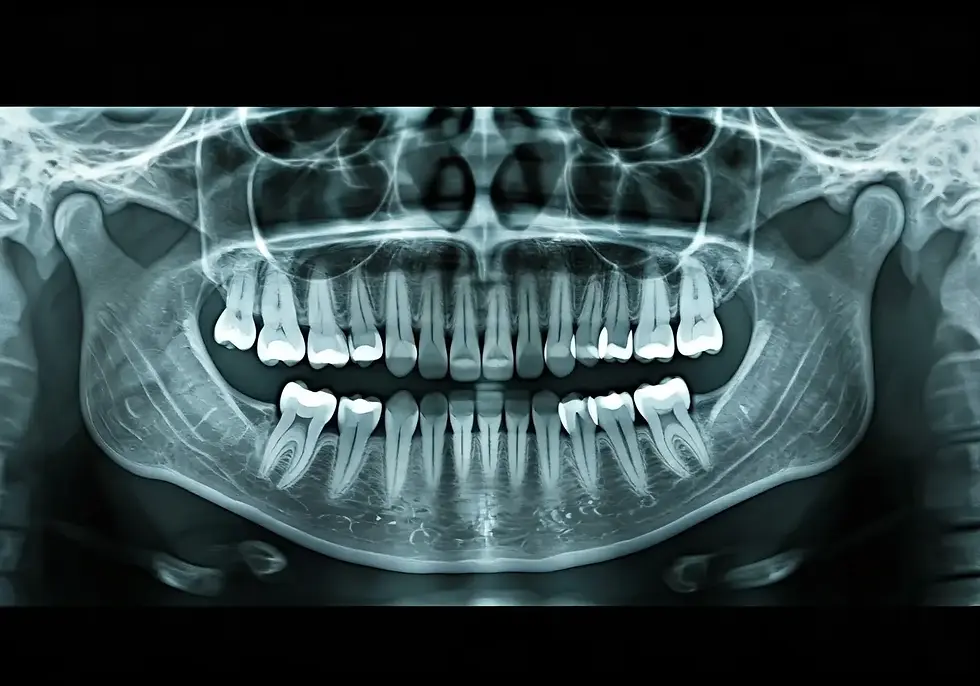

Consult with a dentist or oral surgeon who can evaluate your dental health, take X-rays, and discuss any discomfort or pain you're experiencing to determine the best course of action. They can assess whether your wisdom teeth are at risk of becoming problematic.